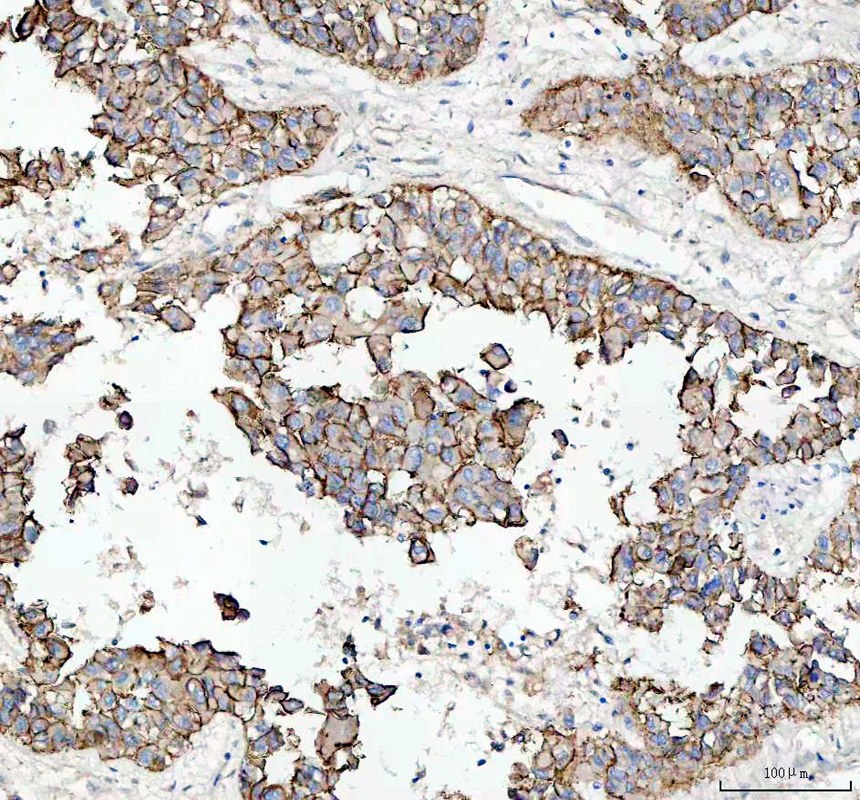

IHC analysis of E-cadherin/CDH1 using anti-E-cadherin/CDH1 antibody (PB9561).

E-cadherin/CDH1 was detected in a paraffin-embedded section of human hepatocellular carcinoma tissue. The tissue section was incubated with rabbit anti-E-cadherin/CDH1 Antibody (PB9561) at a dilution of 1:200 and developed using HRP Conjugated Rabbit IgG Super Vision Assay Kit (Catalog # SV0002) with DAB (Catalog # AR1027) as the chromogen.